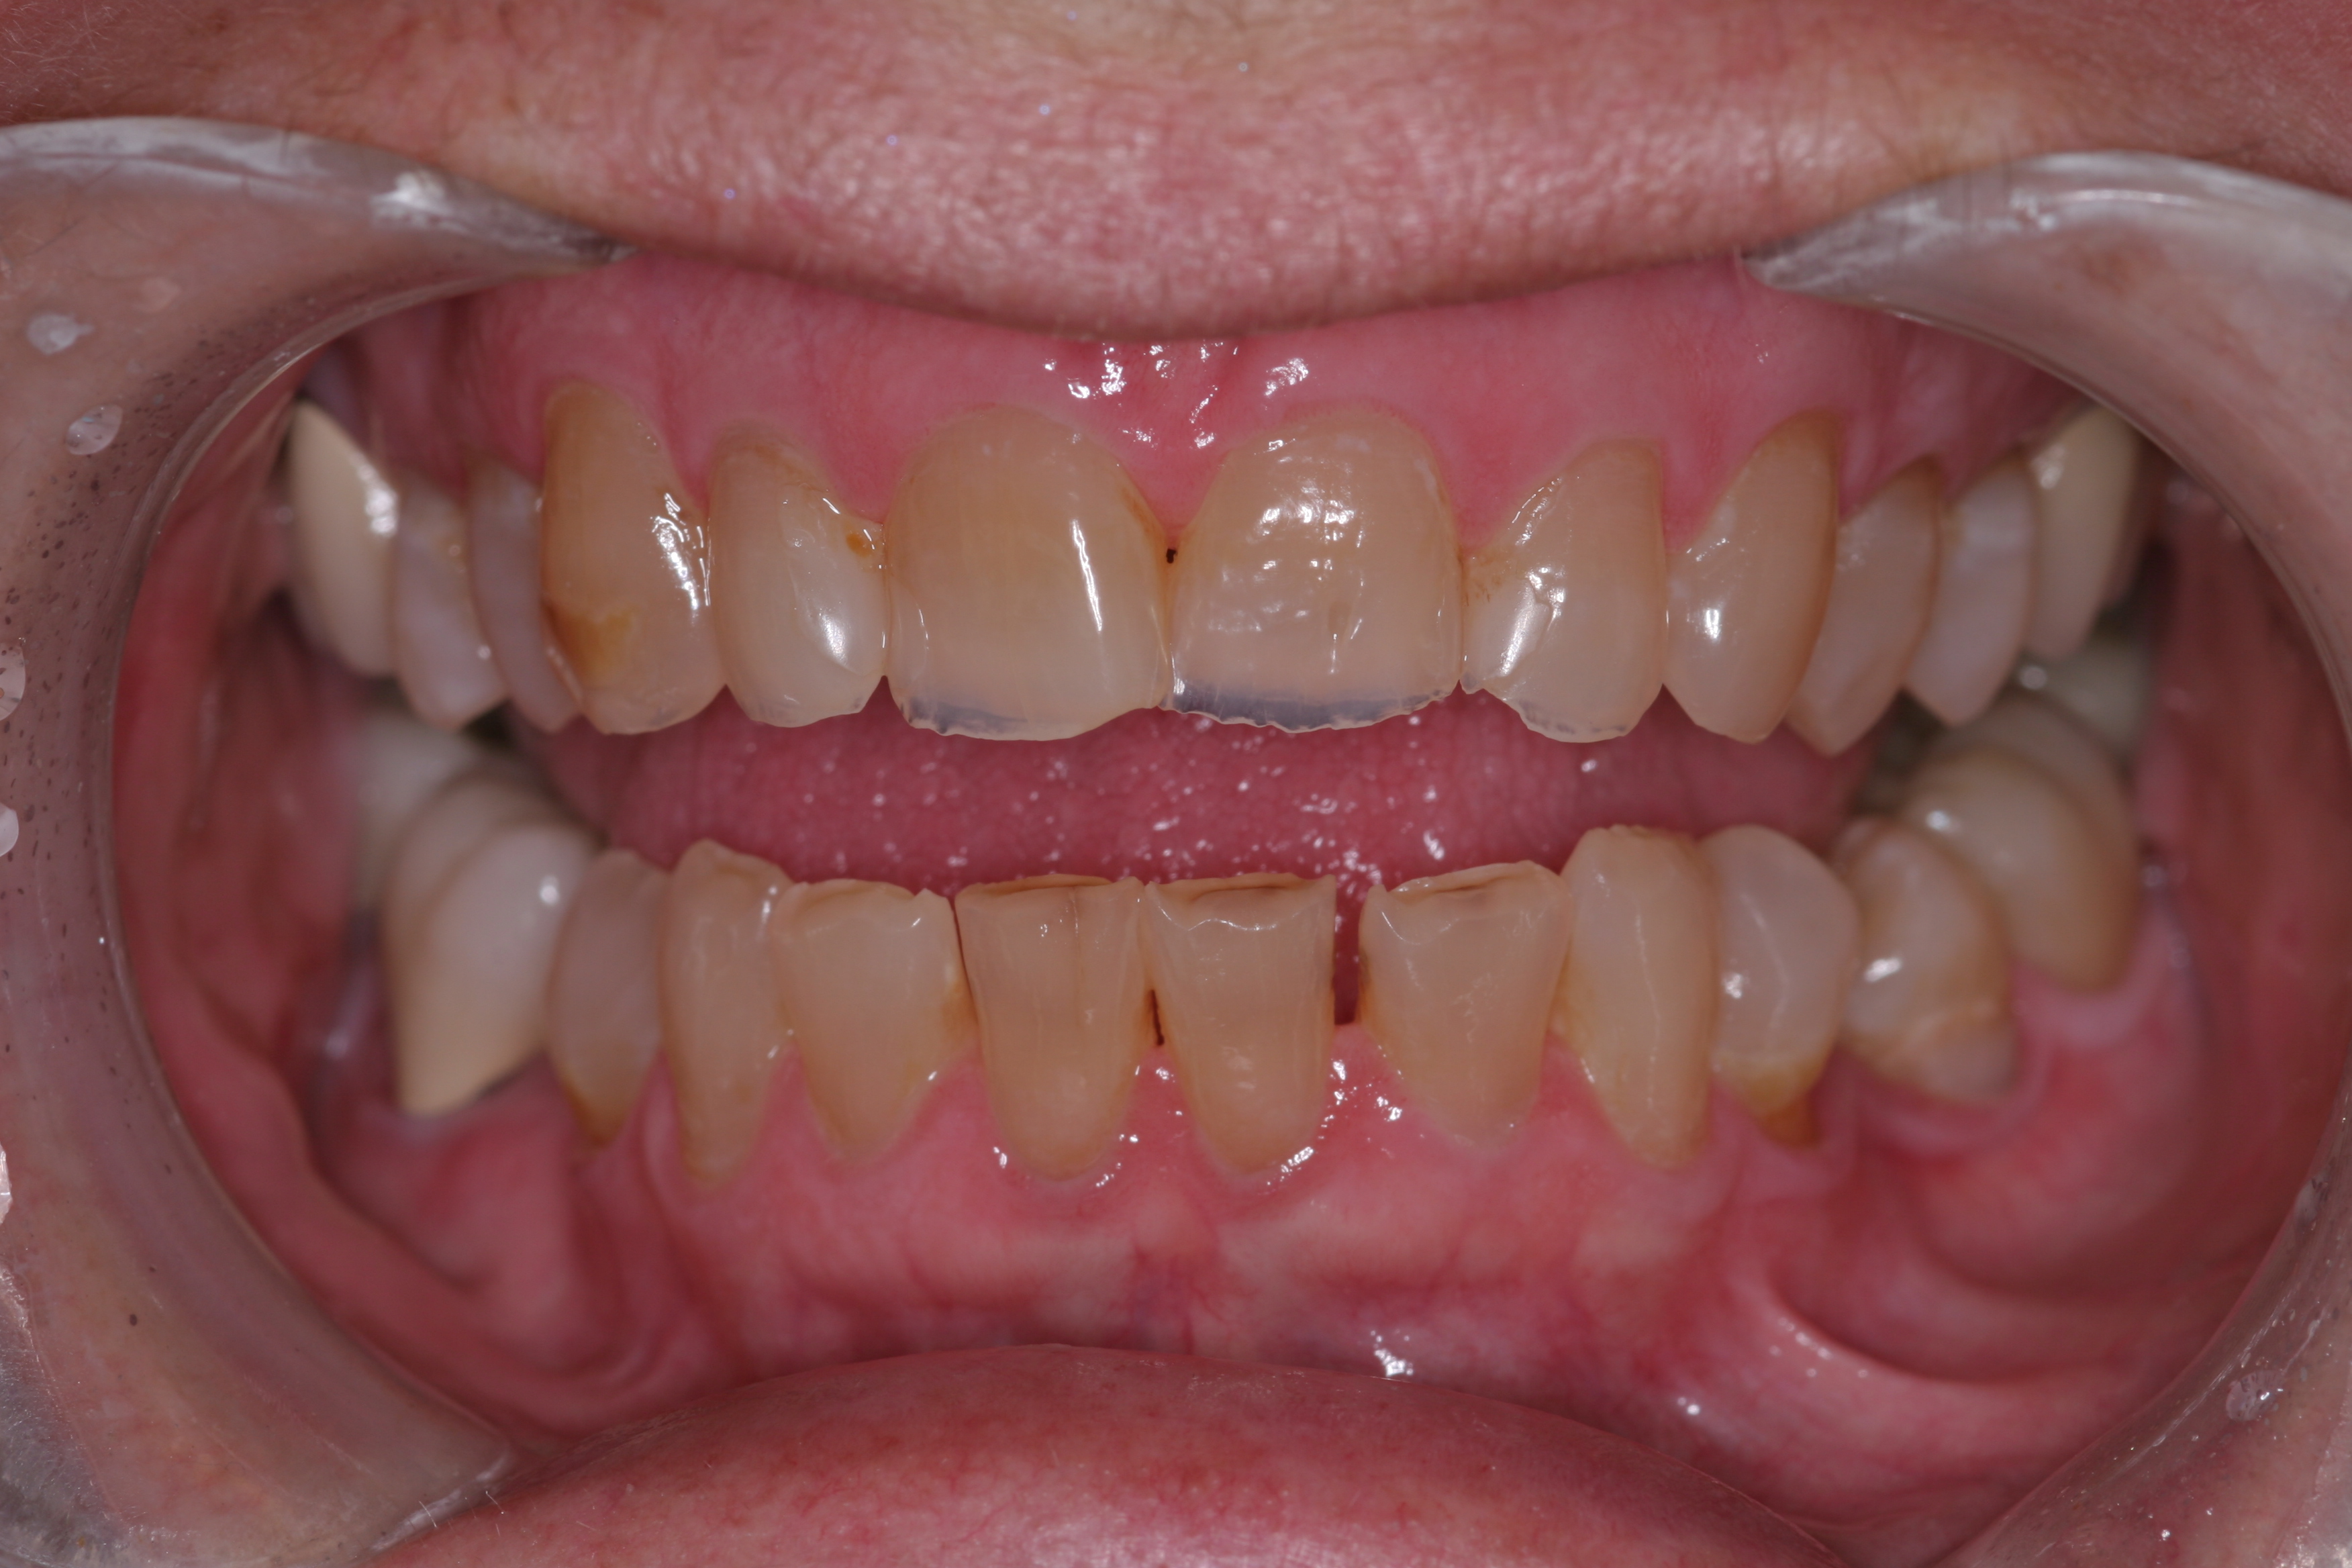

A patient presented with advanced generalized wear of her anterior teeth (Figure 10 and Figure 11). She was displeased with their overall appearance because of their color and wear (Figure 12). A complete examination was performed, revealing instability in her temporomandibular lateral poles bilaterally, sore muscles of mastication, advanced wear, a CR/MIP discrepancy, and loss of her anterior guidance due to the wear. Although the topic is beyond the scope of this article, the patient was also screened for possible sleep apnea. This included an evaluation of the Mallampati score, previous sleep therapy evaluation or treatment, snoring history, an evaluation of her neck size, her weight status, and the presence of the tonsils and their size. In every case, if this clinician suspects airway obstruction to be playing a role in tooth wear issues, the patient is referred to a sleep physician. The patient in this case displayed few apnea risk factors, and the patient’s anterior wear facets fit together like a “lock and key” pattern seen in parafunctional activity. Splint therapy was initiated to stabilize the joints and muscles. A repeatable CR position was verified through load testing. At this point diagnostic models, photographs, a CR bite record, and a facebow were taken and recorded.

(10.) A patient presented with advanced generalized wear of her anterior teeth, and was displeased with their overall appearance because of their color and wear.

Figure 10

(11.) A patient presented with advanced generalized wear of her anterior teeth, and was displeased with their overall appearance because of their color and wear.

Figure 11

(12.) A patient presented with advanced generalized wear of her anterior teeth, and was displeased with their overall appearance because of their color and wear.

Figure 12